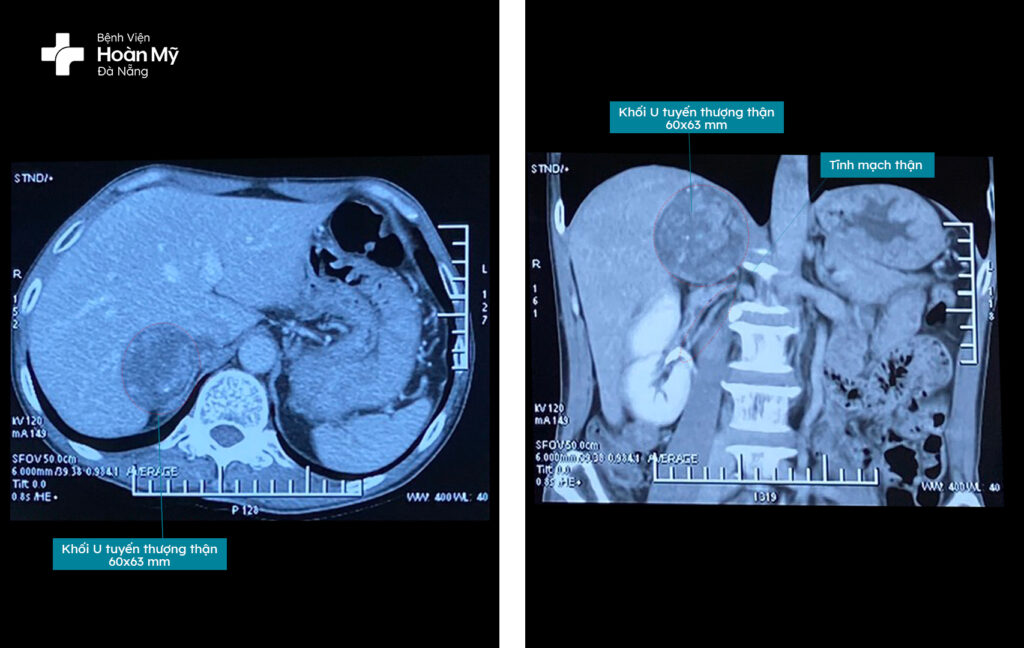

Ngày 9/5/2023, anh N.V.C (55 tuổi, trú tại TP.Đà Nẵng) trong khi thăm khám sức khỏe định kỳ tại Bệnh viện Hoàn Mỹ Đà Nẵng được các bác sĩ phát hiện khối u ở hạ sườn phải. Kết hợp kết quả thăm khám, xét nghiệm, chụp CT, hội chẩn chuyên khoa, bác sĩ Bệnh viện Hoàn Mỹ Đà Nẵng chẩn đoán người bệnh có khối u tuyến thượng thận phải, kích thước (63x60mm) và chỉ định phẫu thuật cắt bỏ u tuyến thượng thận phải.

Bác sĩ Bùi Quốc Triệu – Trưởng khoa Ngoại Tiết niệu – Nam khoa nhận định: “Anh C có khối u tuyến thượng thận phải, kích thước khoảng 6cm. Đây là trường hợp u lành tính, và là u vỏ tuyến thượng thận, kích thước lớn đẩy thận xuống thấp, u nằm sát tĩnh mạch thận, tiên lượng mổ nội soi khó khăn”.

Hình ảnh khối u tuyến thượng thận phải trên CT, u nằm sát, chèn ép tĩnh mạch thận